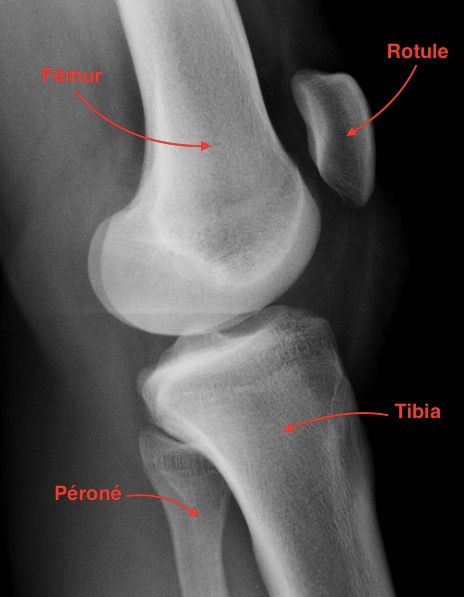

Fichier:Radio profil genou.jpg — Wikipédia

Radiographie de profil du genou gauche | Download Scientific Diagram